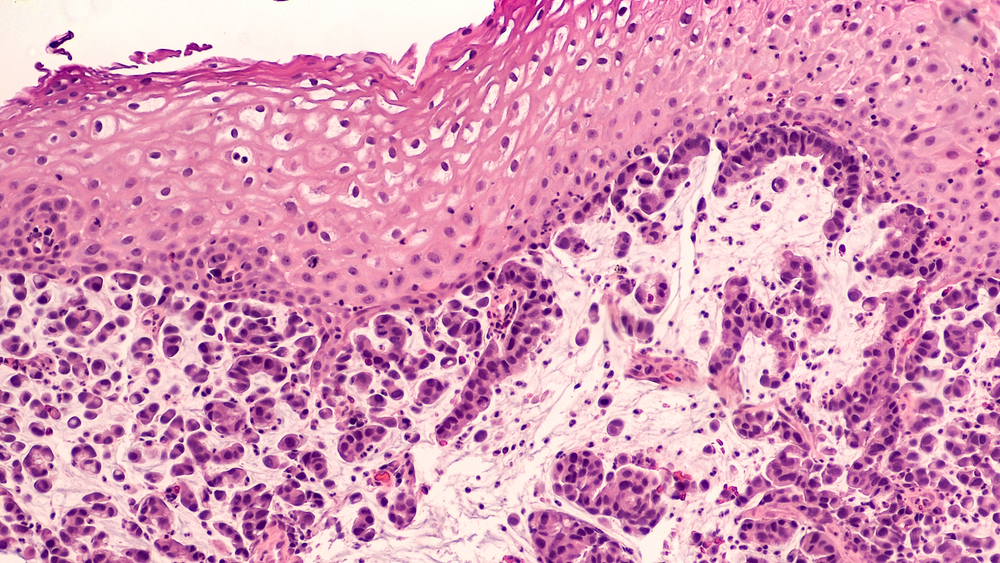

Диагностика рака пищевода проводится под контролем онкологов, гастроэнтерологов. Определить нарушение можно только посредством инструментального обследования. Для выявления патологического процесса чаще всего используется сочетание визуализации (МРТ с контрастным усилением препаратами гадолиния) и биопсии. Биопсия при проведении ФГДС позволяет получить образец пораженной ткани, измененных клеток. После этого образец направляют в лабораторию, где проводится гистологическая оценка (исследование строение фрагмент тканей). По результатам врачи оценивают степень злокачественности патологического очага, а также распространенность рака. Исходя из этих данных, а также анамнеза и жалоб, специалист принимает решение относительно лечения.